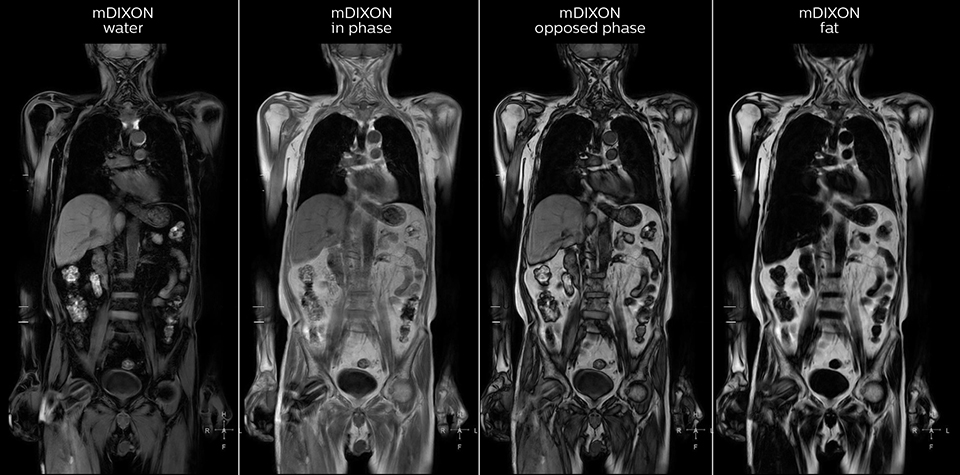

Kawasaki Sawai Hospital’s whole body protocol also includes an mDIXON FFE sequence. Because mDIXON provides images for four contrast types – water only, fat only, in-phase and out-of-phase – from a single acquisition, it is useful in many ways.

“mDIXON FFE allows us to quickly get information we need to assess the presence of fat. That gives us more information when we need to diagnose bone lesions, and when we are asked to judge fat-containing lesions such as hepatocellular or renal carcinoma,” Dr. Nobusawa says.

“The mDIXON fat images can help us to differentiate fatty bone marrow from bone lesions. This is especially useful in elderly people, who tend to have fattier bone marrow. The water images provide a high signal-to-noise ratio in the intestinal canal, which is valuable for visualizing lesions in the colon,” he says.

“In-phase and out-phase sagittal T1-weighted FFE images help us to visualize and further characterize bone lesions such as metastasis and bone-marrow hyperplasia that have high signal on DWI. These images are also used throughout radiotherapy, to monitor changes in the fatty bone marrow.”